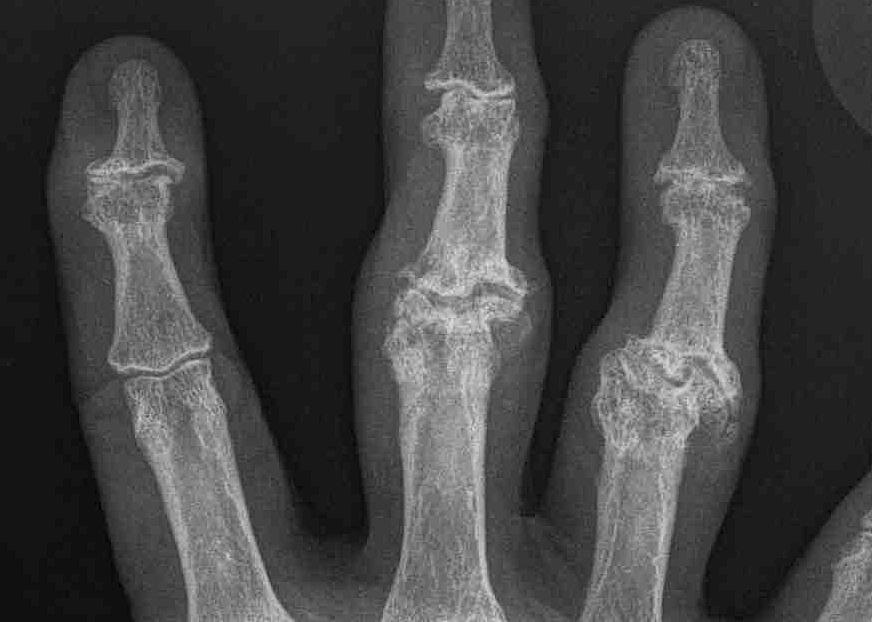

Nalebuff Classification

Function depends upon PIPJ flexion

Type I

- PIPJ passively correctable / regardless of MCPJ position

- Bunnell Test negative

Type II

- PIPJ flexion limited with extension of MCPJ

- Bunnell Test positive

- intrinsic tightness

Type III

- fixed PIPJ flexion regardless of MCPJ position

- joint problem

- lateral bands dislocated dorsal to axis of rotation

Type IV

- joint destruction / X-ray arthritis